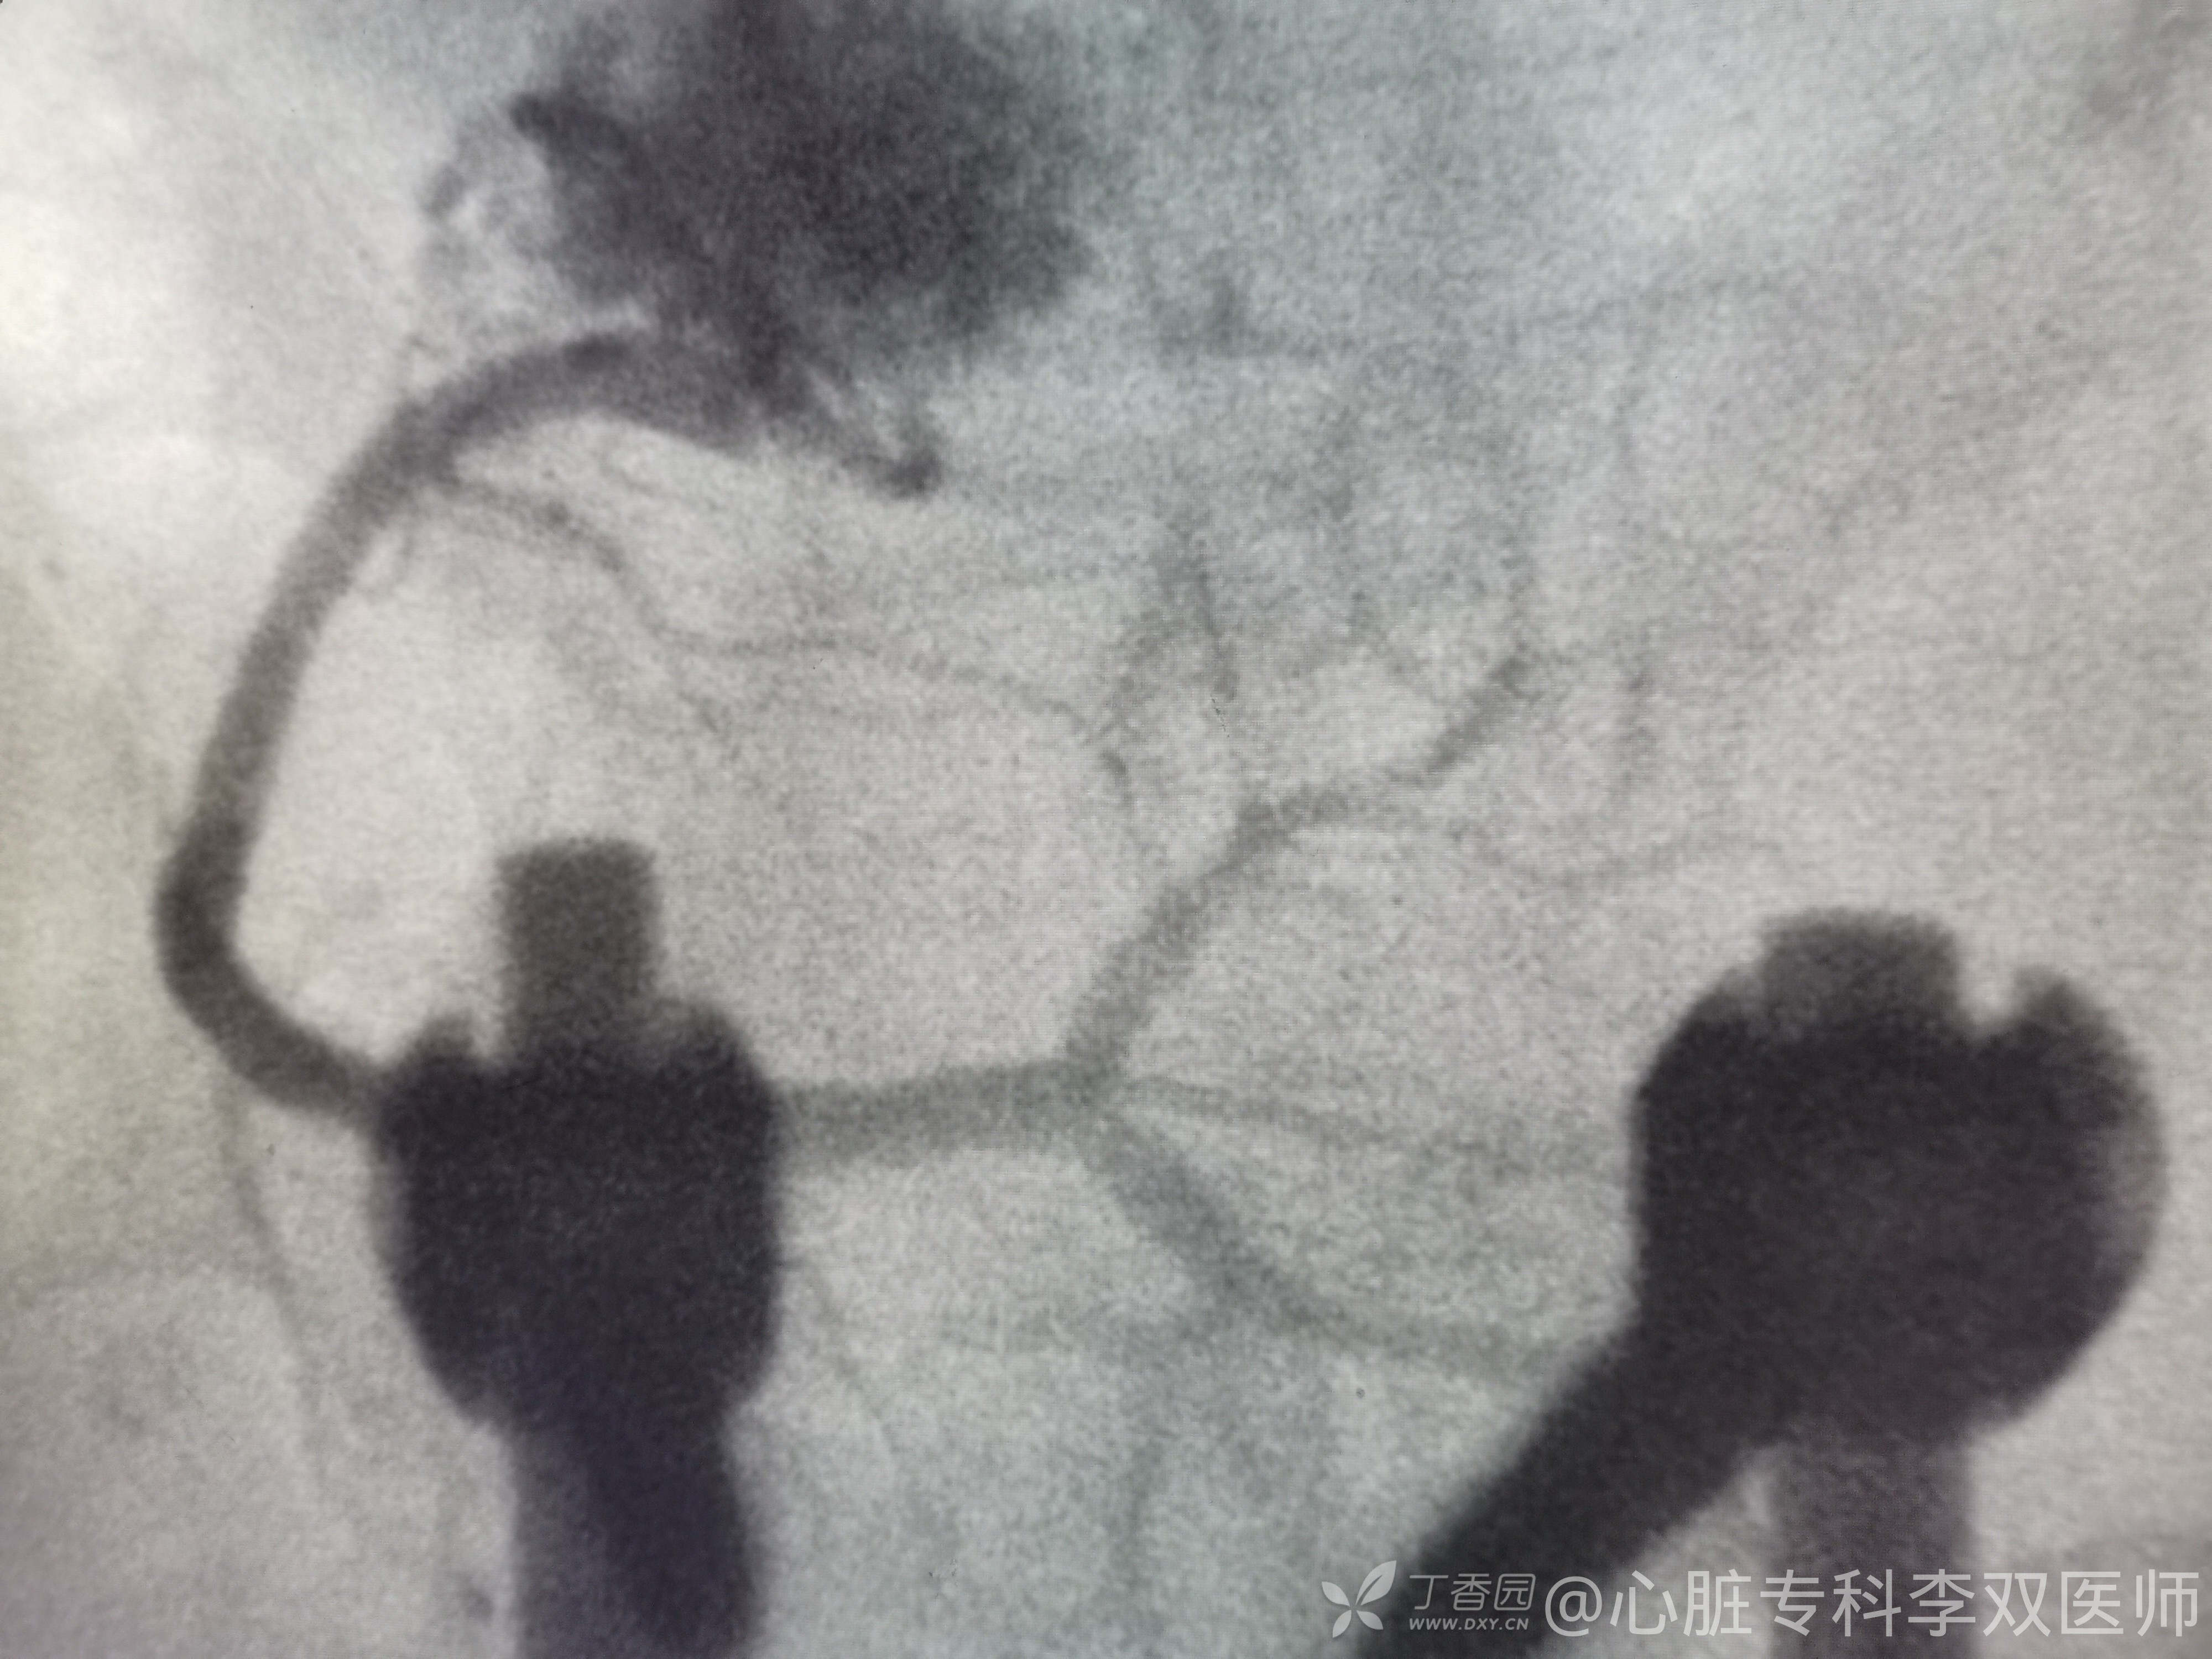

我们会诊考虑确实不能排除心梗,当时做了急诊冠脉造影,不是心梗!(彩超没有报室壁瘤,不过它也排除了血栓,所以才敢打心室造影的)。

心尖部大室壁瘤引起的前壁和侧壁ST抬高,推测患者20年前放支架是急性前壁心梗。